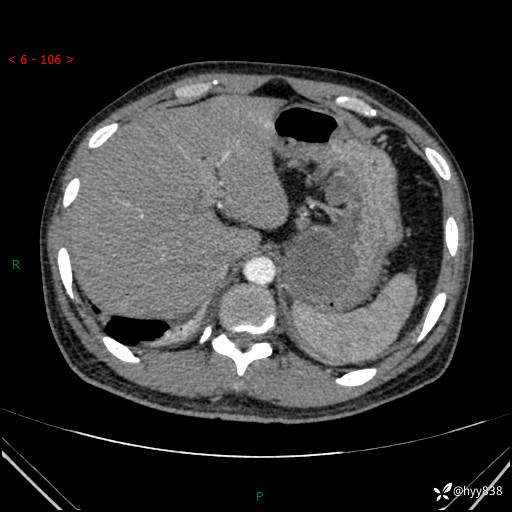

病例39岁/女,左侧腰痛入院。腹腔囊实性肿块,定位、定性---结果公布~

性别:男

年龄:39岁

简要病史:左侧腰痛待查,CT发现腹腔占位

腹部CT平扫+增强